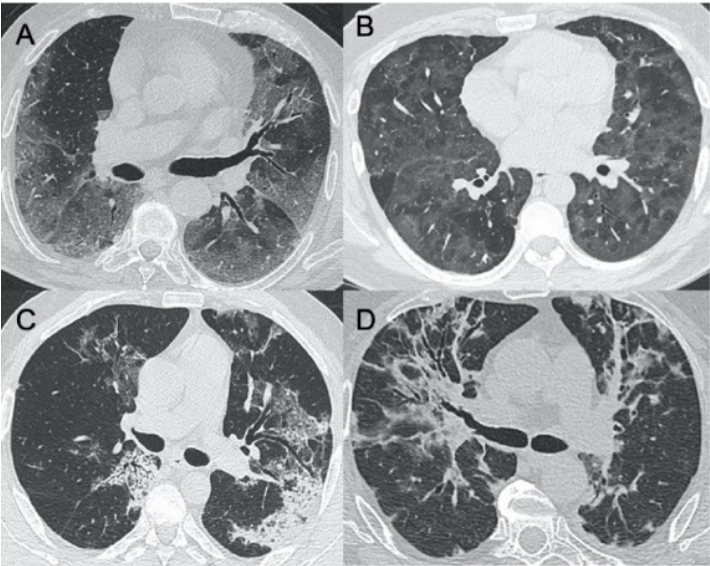

病毒性肺炎是由各种呼吸道病毒感染引发的肺实质炎症,容易并发呼吸衰竭,常见于幼儿(<5岁)和年龄>50岁的成人。WHO数据显示:社区获得性肺炎(CAP)中病毒性肺炎占20%~40%,在ICU中比例稍高,为30%~40%。常见病毒性肺炎的病原体包括流感病毒、鼻病毒、呼吸道合胞病毒、腺病毒、人偏肺病毒、巨细胞病毒、冠状病毒等。病毒性肺炎的常见影像学特征如下:图1所示为COVID-19的高分辨率CT(HRCT):在急性期,图1A为双肺弥漫性磨玻璃影(GGO),图1B为小叶周围型,图1C和D表现为亚急性间质性肺炎,GGO减少,主要为胸膜下局灶性实变和小叶间/小叶内间质增厚。图2A-C显示了一例与COVID-19间质改变相似的甲型流感病例:GGO主要分布在胸膜下和双侧,呈小叶周围性分布。图2D为同一患者的仰卧位胸片,可见弥漫性肺间质受累。图3A-D为一例H1N1相关肺炎并发急性呼吸窘迫综合征(ARDS)的影像,可见弥漫性、双侧GGO以及牵拉性支气管扩张。图4A显示了一例急性腺病毒肺炎,具有典型的多灶性和大叶GGO,图4B-C显示其导致的长期后遗症——Swyer–James综合征的表现。图5所示为一例疱疹病毒性肺炎,可见双侧分布呈斑片状的GGO(主要位于两肺上叶)。一项基于对美国大规模人群分析的前瞻性多中心研究显示,病毒性肺炎的患病率和发病率随年龄而异,其累积发生率约为22%。研究纳入2222例儿童,其中66%(共1472例)报告有病毒感染,在155例(7%)病例中发现病毒和细菌合并感染。事实上,呼吸道病毒、腺病毒和人偏肺病毒在5岁以下儿童中比较常见。在同一研究的2259例成年人患者中,只有853例(38%)患者检测到病原体,530例(23%)患有病毒性肺炎,59例(3%)发现合并感染。